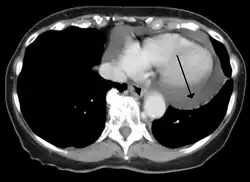

Cardiac CT and MRI scans: cross-sectional imaging with computed tomography (CT) can help localize and quantify the effusion, especially in a loculated effusion (an effusion contained to one area).[12] CT imaging also helps assess for pericardial pathology (pericardial thickening, constrictive pericarditis, malignancy-associated pericarditis).[1] Whereas cardiac MRI is reserved for patients with poor echocardiogram findings and for assessing pericardial inflammation, especially for patients with continued inflammation despite treatment.[5] CT and MRI imaging can also be used for continued follow up on patients.

A CT scan showing a pericardial effusion -